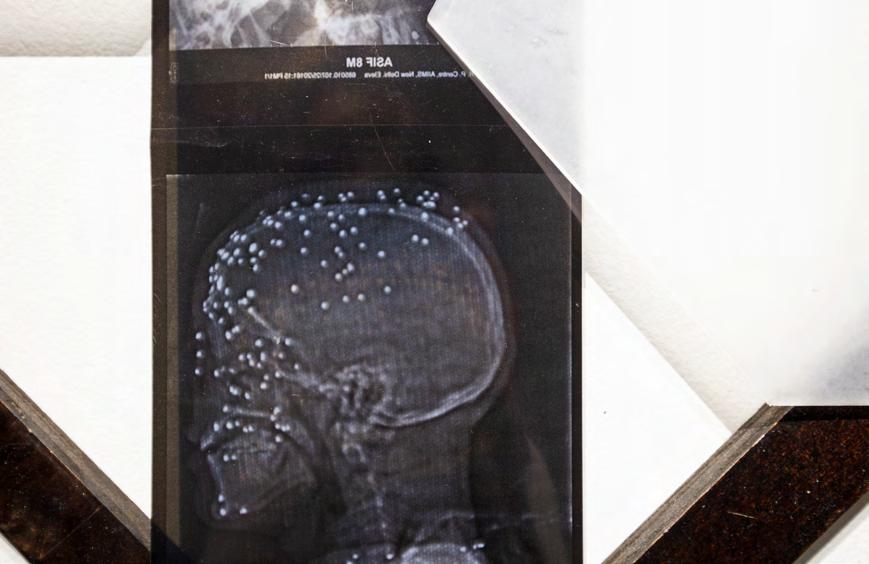

Others look back, perhaps as a way to anticipate what’s next. In adjacent galleries were document-based installations by Blush Berrios, Liv McGuinness and Basharat Ali Syed. These artists take the ephemera of a lived experience and craft narratives about ancestry and family trauma. Especially personal was McGuinness’s juxtaposition of documents that trace her birth in Vietnam to her upbringing by a white Long Island family. She deftly plays with cultural signifiers but also the complex emotions that come from both adoptees and immigrants. Similar to these projects is Rhesa Paul’s brilliant blue installation of jars and baskets that unites the personal and historical in a